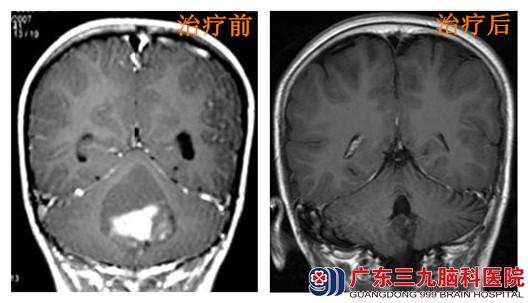

【后颅窝髓母细胞瘤治疗后8年无复发】

今年年仅13岁的石头(化名),在4岁时无明显诱因出现头晕,当地卫生所给予对症处理后症状缓解,未作进一步处理。后于2007年上述症状再次发生并加重,伴恶心呕吐及行走不稳。当地人民医院查头颅CT提示:后颅窝占位性病变,梗阻性脑积水。患者遂到广东三九脑科医院就诊,查体:神志清楚,精神可,智力正常,语言正常,体型消瘦。双眼活动良好,闭目难立征+,行走不稳诊断后颅窝占位病灶,考虑髓母细胞瘤可能性大。于急诊在全麻下行“脑室钻孔外引流术”,手术顺利,后在全麻下行“后颅窝占位性病变切除术”,术后病理回报:髓母细胞瘤(WHO IV级)。恢复后再行残留病变放疗,并全中枢预防放疗,放疗后疗效评价PR,放疗期间同步低毒化疗2程。

之后患者坚持每年复查,目前治疗后将近8年,复查情况良好,未见复发征象。今年患者已经13岁,学习处于中上水平。